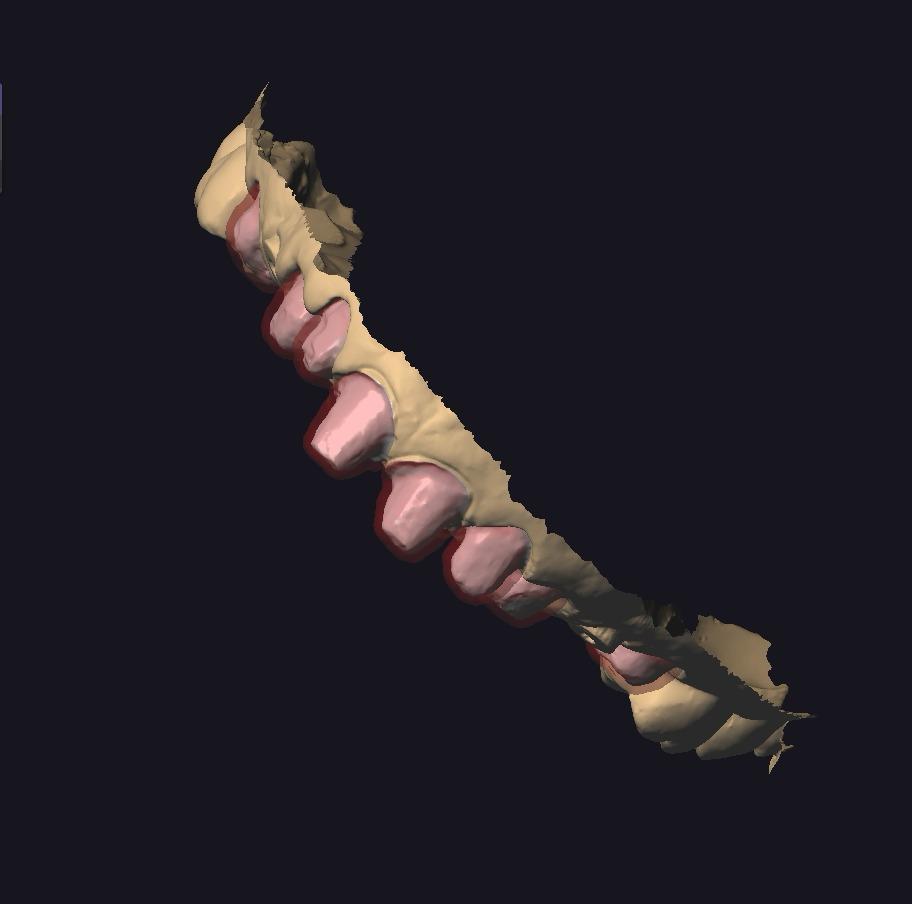

ZIRKONYUM ALT YAPI

IMPLANT USTU ZIRKONYUM ALT YAPI